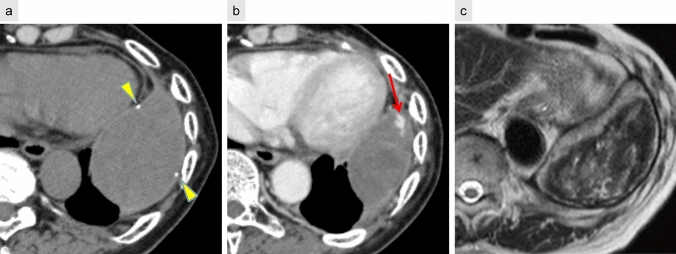

Chronic expanding hematoma

Chronic expanding hematomas are uncommon but clinically significant late postoperative complications. They may present as slowly enlarging, space-occupying lesions that persist over months to years and can mimic malignancy on imaging. These lesions are frequently associated with a history of thoracic surgery for conditions such as tuberculosis, pneumothorax, trauma, or tuberculous pleurisy [25].

CT typically reveals a well-defined, encapsulated mass with peripheral calcification. Contrast-enhanced CT may demonstrate scattered small nodular enhancement at the lesion margins. On T2-weighted MRI, the “mosaic sign” has been reported as a characteristic feature, reflecting heterogeneous signal intensities due to the presence of both acute and chronic hemorrhagic components [26] (Fig. 11).

Fig. 11.

Chronic expanding hematoma. Five years following left lower lobectomy, non-contrast CT (a) reveals a mass with a focal calcified component (arrowhead) within the capsule. Contrast-enhanced CT (b) shows a small nodular enhancement at the lesion margin (arrow). T2-weighted MRI (c) demonstrates a mosaic pattern with areas of high and low signal intensity, characteristic of the “mosaic sign”